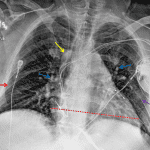

- Right IJ approach central venous catheter with tip projecting over the right atrium

- Left subclavian approach cardiac rhythm maintenance device with leads projecting in the right atrium, right ventricle, and coronary sinus

- Mild interstitial pulmonary edema with faint groundglass opacification in the left lung base

- No pleural effusion or pneumothorax

- Mild enlargement of the cardiopericardial silhouette

- Mild interstitial pulmonary edema

Cardiomegaly with mild interstitial pulmonary edema and likely early alveolar edema in the left lung base.

No pleural effusions.